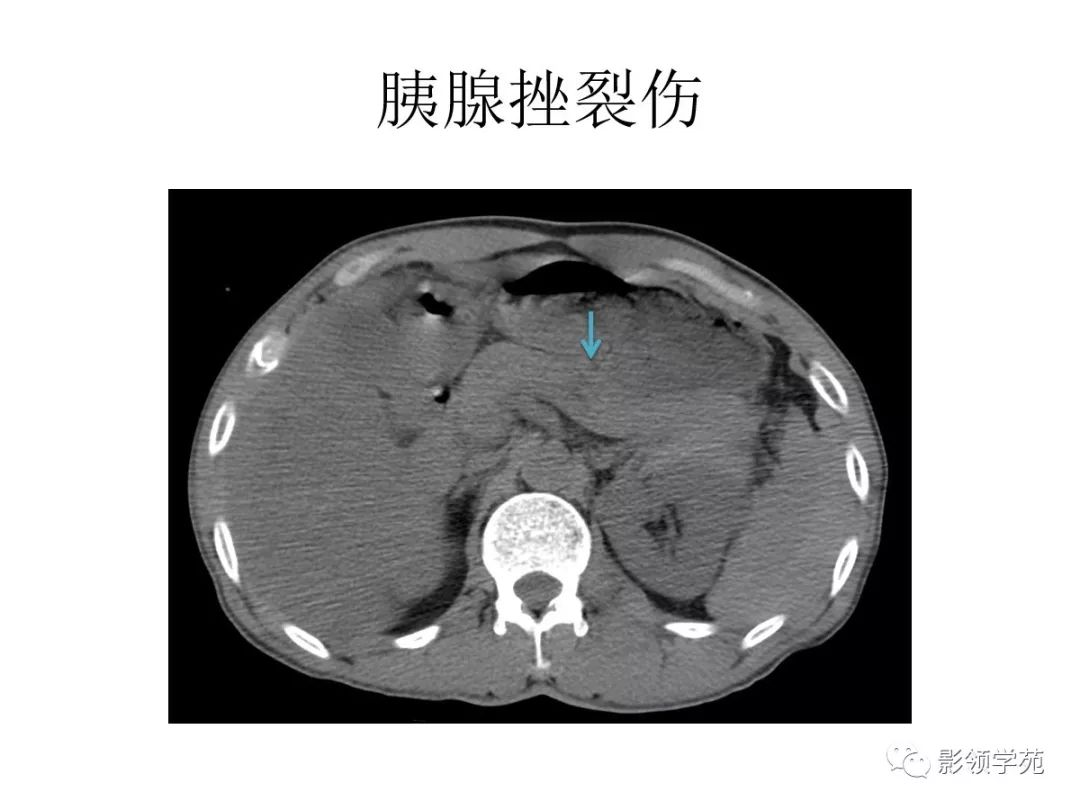

病例结果:右侧多发肾裂伤编辑/校对:郑孝飞增强ct男,46岁,因"外伤后

图片尺寸960x720